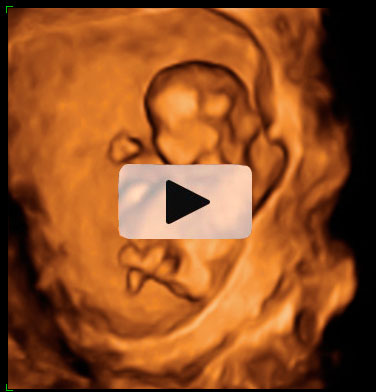

Ecografía Embarazo 4D Semana 12 - ANOMALÍAS CROMOSÓMICAS